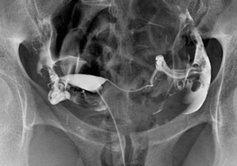

Radio hanche bébé doctolib-5 av Fontaine Ste Marguerite 000 Auxerre Tel 03 45 02 55 50 fax scanner 03 86 46 23 16 Prendre rendezvous Prendre rendezvous Centre d'imagerie médicale Auxerre Notre activité notre équipe médicale92 Hanche COXOMÉTRIE Ce sont les mesures angulaires du cotyle et du col fémoral COXOMÉTRIE STANDARD Radiographie du bassin de face debout et faux profil de hanche (Lequesne) Sur le cliché de face, on mesure l'obliquité du toit acétabulaire, l'angle cervicodiaphysaire et la couverture latérale de la tête fémorale (Fig 101a) Fig 101

RDV Doctolib ou 01 42 29 56 06CENTRE DE RADIOLOGIE DE LA MAIRIE Prendre rendezvous sur Doctolib Tél 01 46 45 06 13 Fax 01 41 08 94 77 32, rue Diderot IssyLesMoulineaux Voici les radios d'une arthrose de hanche très évoluée, avec tous les signes radiologiques classiques que l'on peut observer Cidessus, vous pouvez voir les radios de la hanche gauche de face et de profil Cidessous, vous trouverez une radio du bassin de face avec quelques annotations pour vous indiquer les signes à voir